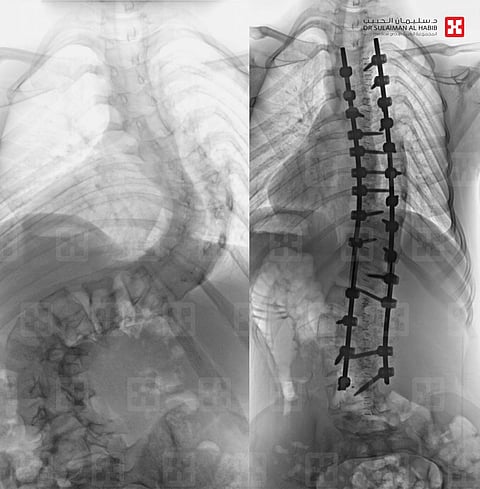

أجرى قسم جراحة العمود الفقري بمستشفى الدكتور سليمان الحبيب بالقصيم 4 عمليات ناجحة، لتقويم العمود الفقري وتثبيت ودمج الفقرات، خلال 48 ساعة لأشخاص مصابين بالجنف، وأنهت هذه العمليات معاناة المرضى مع أعراض ومضاعفات المرض التي اتسمت بالحدة والتنوع.

وقال د.صلاح الدين خليفة استشاري جراحة العمود الفقري بالمستشفى: إن الحالات التي تمت معالجتها تفاوتت درجة الانحراف عندها بين 45 إلى 90 درجة، وتراوحت أعمارها بين 11 إلى 38 سنة، وعانى بعضها من أعراضٍ كبروز الظهر، وعدم تساوي الكتفين والخصر، وبروز أحد الوركين وجانب من القفص الصدري، وصعوبة ممارسة الحياة اليومية بصورة طبيعة.

وأضاف د.خليفة أن أكثر الحالات تعقيدًا، حالةٌ تعود إلى سيدة عمرها 38 سنة، وبلغت نسبة الانحراف عندها 90 درجة، وتكللت عمليتها -ولله الحمد- بنجاح كبير، وأكد أن المريضة بدأت في الوقوف والتحرك في اليوم الأول للعملية، كما أنها استعادت المظهر القويم، بعد تعديل وضعية الحوض والكتف، إضافة إلى أن طولها مع النجاح الكبير للتعديل زاد بنحو 6 سم، وخرجت من المستشفى وهي بصحة جيدة بعد أن أمضت 6 أيام قيد التنويم والعناية الصحية الحثيثة.

واستطرد د.خليفة أن باقي المرضى وهم فتاتان وفتى واحد، كانت درجات انحراف العمود الفقري لديهم أقل حدة، وخضعوا لعمليات تعديل ناجحة، وجميعهم -بمن فيهم الحالة الأولى- استطاعوا التحرك على أرجلهم في ذات يوم العملية، وتخلصوا من كل الأعراض التي قادتهم إلى المستشفى بعد فترة قصيرة من إجراء العملية، وعادوا إلى الحياة الطبيعية.